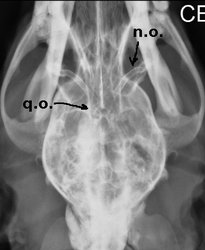

Los nervios ópticos (n.o.) y el quiasma óptico (q.o) se pueden observar en una ventriculografía (radiografía con contraste yodado aplicado en cisterna magna). Recordemos que los nervios ópticos están envueltos por meninges y por ende por líquido cefalorraquídeo.

Es fácil visualizar en la ventriculografía también el tronco encefálico (t.e)